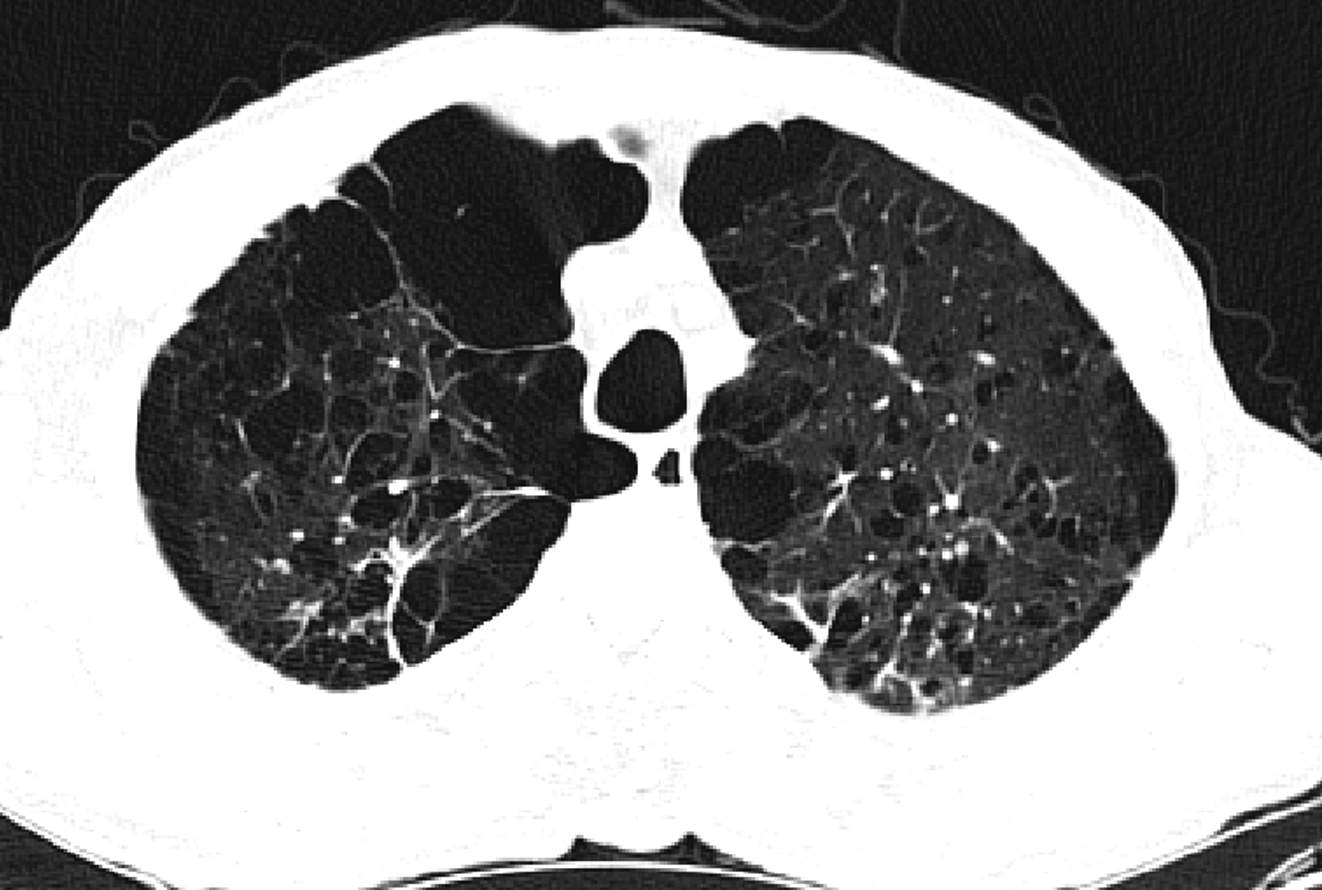

因CT明显异常而复诊。

因患者有肺大泡,肺功能存在一定禁忌。